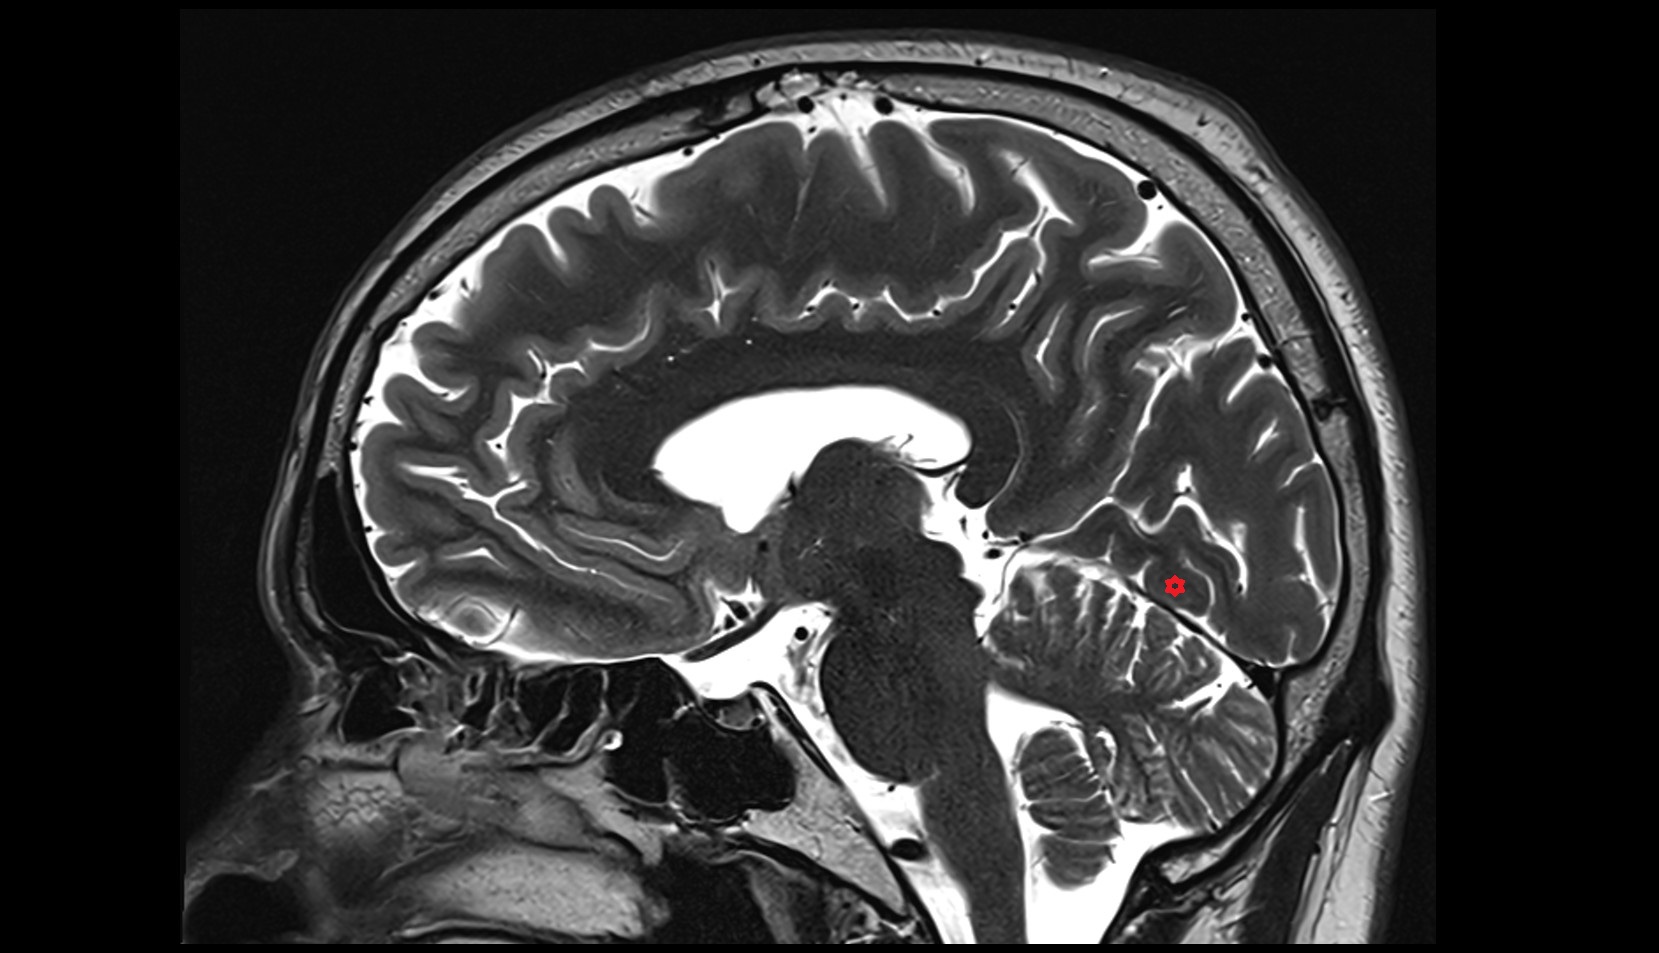

- Cerebellum